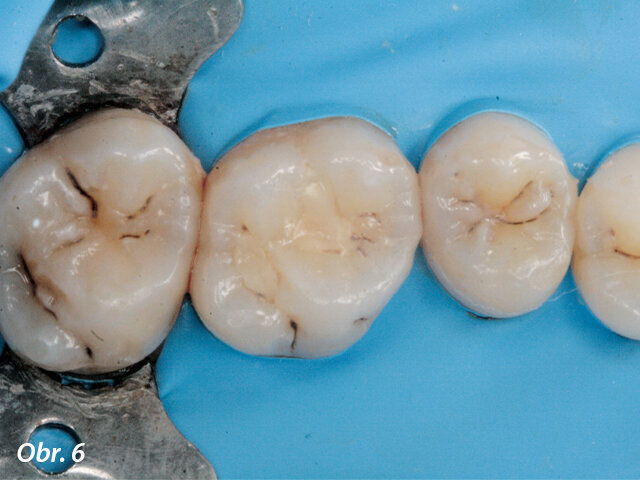

Kazuistika

Pacientka ve věku 38 let přišla do mé ordinace kvůli vyřešení zubních kazů. Při klinickém vyšetření nebyly patrné žádné kazy velkého rozsahu (obr. 1, 2). Až na RTG snímcích typu bitewing (obr. 3, 4), nezbytného prostředku pro diagnostiku v záchovné stomatologii, byly vidět mnohé kariézní léze, které zasahovaly do dentinových tkání. Pacientka požadovala vynikající estetický výsledek, což znamenalo sladění kompozitního materiálu se sklovinnými tkáněmi. Tento požadavek musel být zkombinován s funkční rehabilitací, která by v distálním úseku odolala zatížení žvýkacími silami a zajistila dlouhodobě minimální možné opotřebení. V rámci léčebného plánu bylo pacientce navrženo řešení v podobě přímého ošetření kazů v jednotlivých kvadrantech a nepřímé výplně v zubu 47, které by umožňovalo nejlepší přesnost okrajů a bylo zárukou dlouhodobě vynikajícího výsledku.